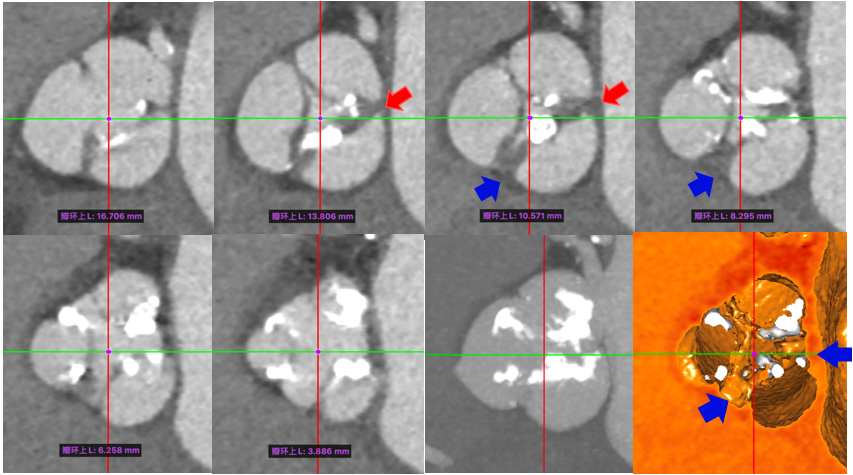

典型病例1

手术由首都医科大学附属北京安贞医院心内科周玉杰副院长、心外科张海波教授、心内科刘巍教授及其团队组成的TAVR心脏瓣膜团队共同完成。中国医学科学院阜外医院吴永健教授、四川大学华西医院冯沅教授、复旦大学附属中山医院潘文志教授等与会专家深度参与手术相关步骤的讨论和技术交流。